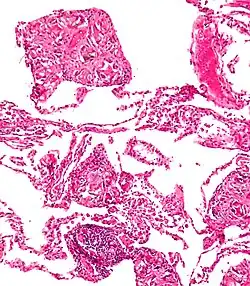

Surgical suture. H&E stain.

Splinters are common foreign bodies in skin. Staphylococcus aureus infection often causes boils to form around them.[11]

Talcosis of the lung due to intravenous drug use. H&E stain.